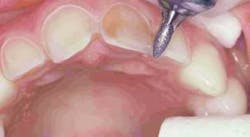

Preparation of the four incisors was then initiated using diamond burs from the Shofu Contemporary Cutting Kit (Figure 5). With the high-speed ElectroTorque KaVo handpiece, a small round diamond (0872-1) was used to outline the peripheral margins of the preparations (Figure 6). By scoring the facial surface of the incisors with the depth cutter (0897-1) (Figure 7), smooth and uniform tooth structure removal using a coarse tapered diamond (0835C-1) was facilitated (Figure 8). As tooth nos. 9 and 10 were prepared, it came time to address the gingival contour issues of the inflamed interproximal gingiva.